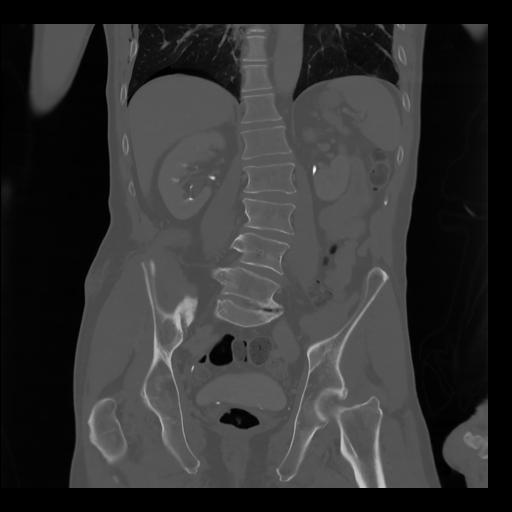

35 CUERPO,CE,Coronal,3.000,CUERPO,Coronal,